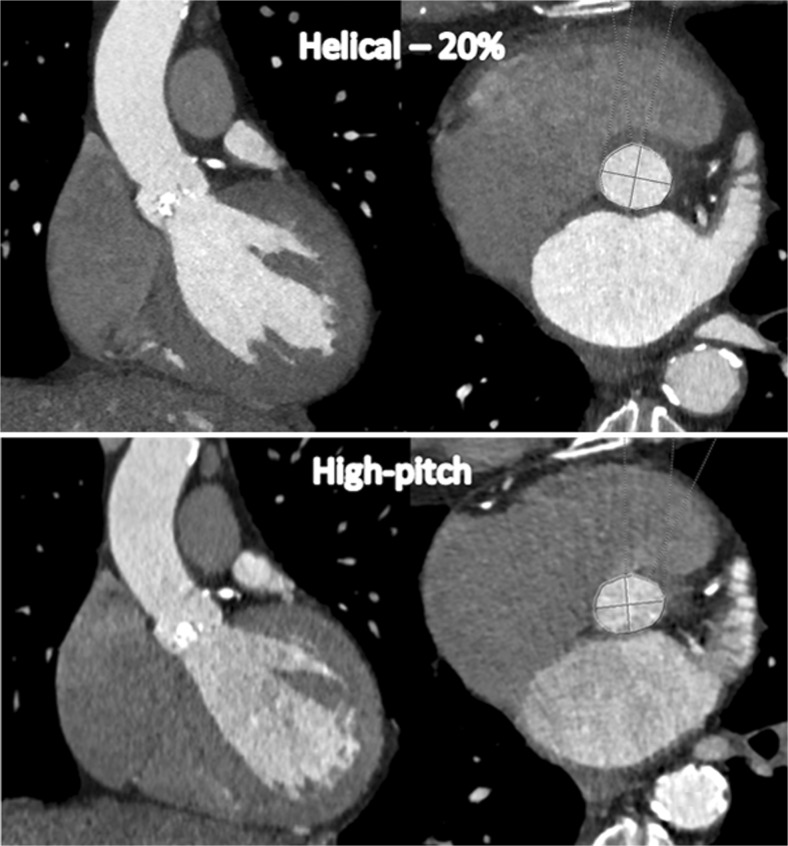

Azzalini et al. [38] tested the feasibility of an ultralow CM volume injection (20 ml = 7.4 gI with 370 mg/ml), in combination with a high-pitch scan mode in 8 patients. They found acceptable image quality using a 100- or 120-kVp setting (automated tube voltage setting according to patient body size). However, in these studies, only one scan — a high-pitch spiral acquisition — was performed for the evaluation of both aortic root and iliac dimensions, which compromises the dynamic assessment of the aortic valve and the annulus as retrospectively gated CTA — including a 20 % phase reconstruction — is recommended [17]. Figure 5 demonstrates the difference in dimensions of the annulus and valve between a 20 % phase reconstruction from a retrospective ECG-gated helical acquisition and a reconstruction from a high-pitch acquisition — as the latter provides no 20 % phase reconstruction. ECG-triggered high-pitch CTA is usually acquired during the diastolic phase, and should, therefore, be used exclusively for aorto iliofemoral CTA [2, 18, 36]. Although differences between phases of reconstruction might be small, they will lead to different measurements for the diameter and could, therefore, lead to different prosthesis sizing [17].

Fig. 5.

Images show the difference in the dimensions of the annulus and valve between reconstruction at the 20 % phase of the cardiac cycle using retrospective ECG-gated helical acquisition (upper) and reconstruction using the non ECG-gated high-pitch acquisition (bottom). The measurements for short and long diameter as well as perimeter were: 21 mm, 25 mm and 4.2 cm2, respectively for the helical acquisition and 19 mm, 24 mm and 3.8 cm2, respectively for the high-pitch acquisition